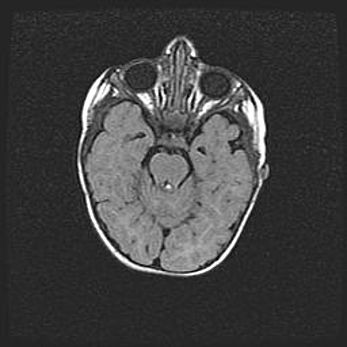

Неполная лизэнцефалия (пахигирия). Открытая гидроцефалия.

Возраст: 17 дней

Вес: 3110 г

Пол: мужской

Окружность головы: 33,5 см

Срок гестации: 35-36 недель

Лизэнцефалия—недоразвитие корковой пластинки и мозговых извилин в результате нарушения миграции нейронов коры. Поверхность мозговых полушарий гладкая. Микроскопически выявляется отсутствие нормальных слоев коры и скопление групп нейронов в подкорковом белом веществе.

Пахигирия—уменьшение числа вторичных извилин. В пораженном полушарии нервные клетки образуют толстый недифференцированный слой с неправильно расположенными нервными волокнами и группами гетеротопных клеток. Нервные клетки незрелые. Белое вещество истончено. При этом нередко аномально развит корково-спинномозговой путь.